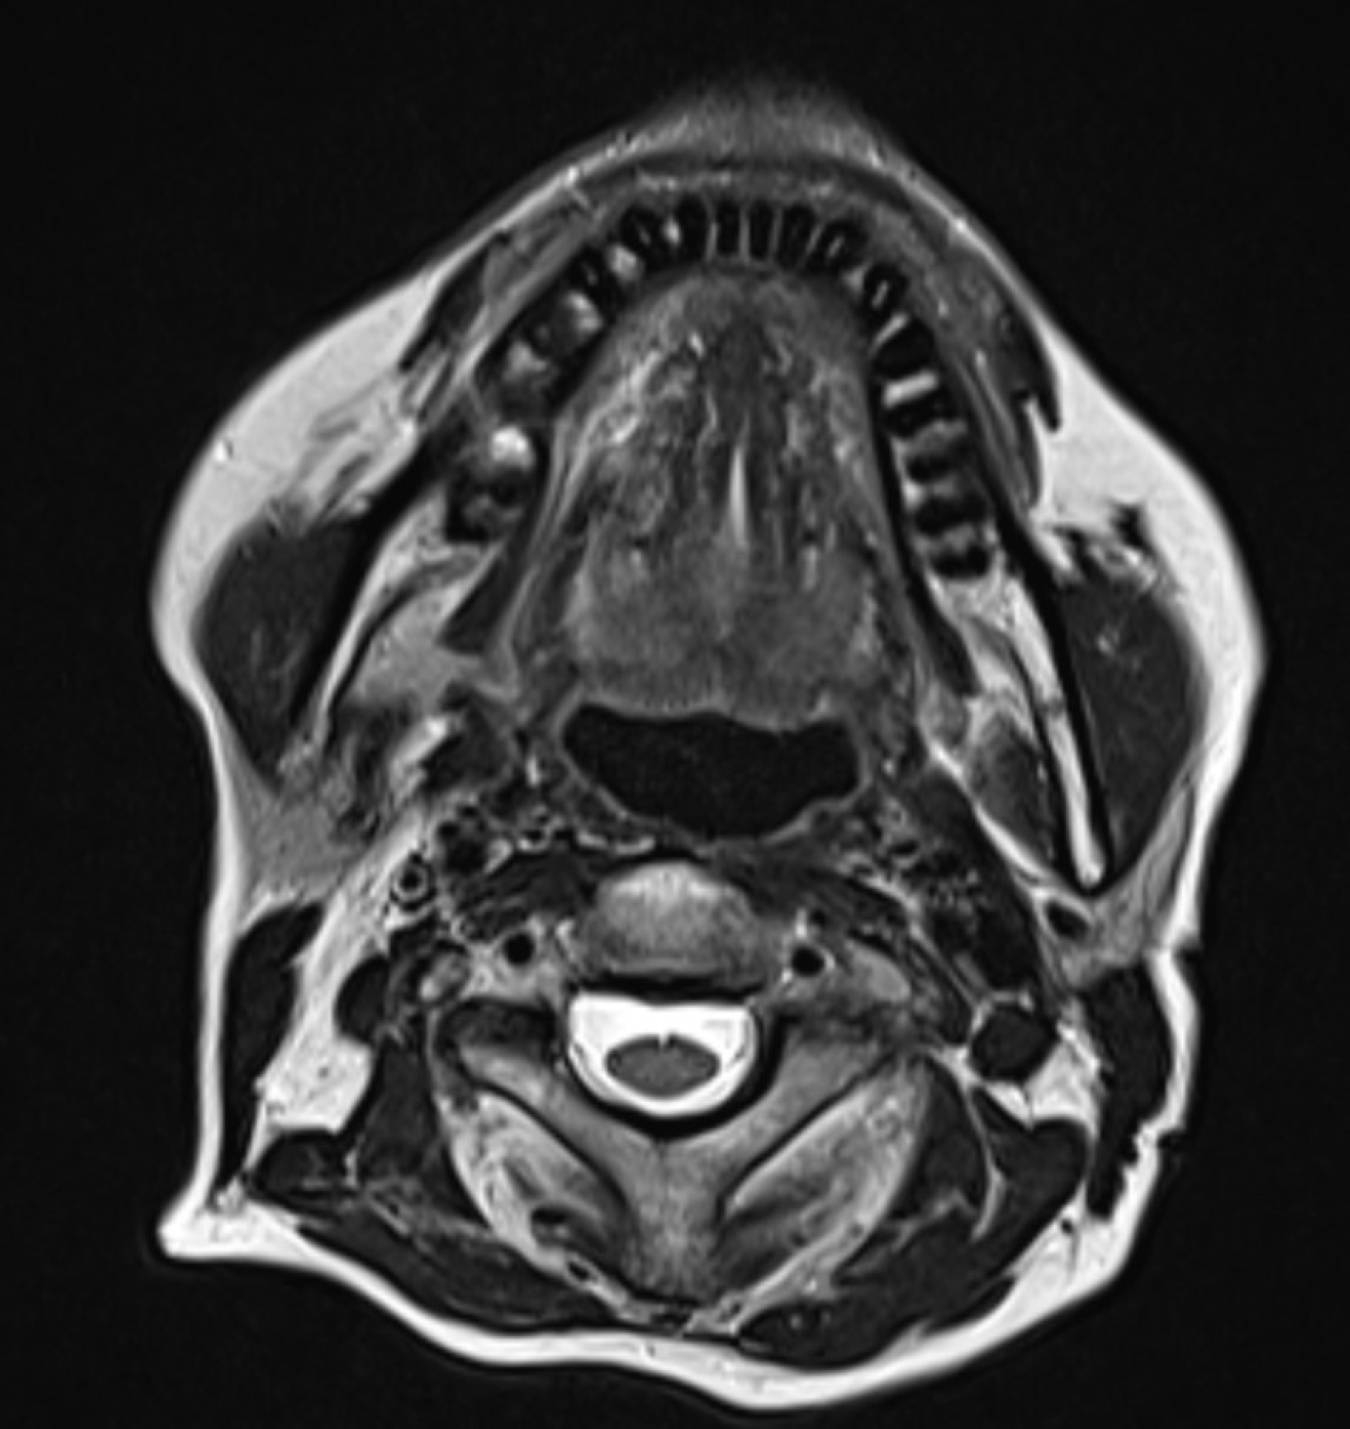

Die (MRT) scanCT Scans von menschlichen Kopf auf einem Ultraschall from www.alamy.de

Die (MRT) scanCT Scans von menschlichen Kopf auf einem Ultraschall ich war beim MRT heute weil ich Wahrnehmungsstörungen bekommen habe und Kopfschmerzen CT vor 2 Wochen Negativ und jetzt MRT auch negativ aber wurde ohne Kontrastmittel gemacht Die Hauptindikationen für die Diagnose: Schlaganfall (hämorrhagisch, ischämisch).